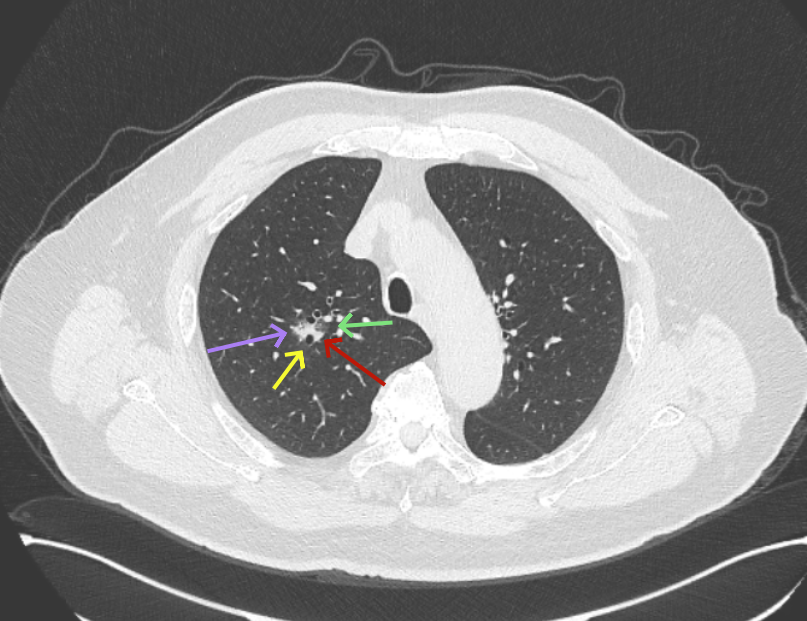

再看2026年3月最近复查时不同层面病灶A的细节影像特征:

微小血管走向病灶,磨玻璃的密度淡而较纯。

病灶A以及他处磨玻璃结节其实进展都是不明显的,略与2022年比,病灶A稍显明显点。病灶B开始时极淡,之前进展虽有但也甚微,直到2025年9月仍是磨玻璃成分为主,只是点状少许密度稍高成分。但在最近半年内却显然进展!若从影像上判断,基本上就得是浸润性腺癌了。那有几点:一是必不能再随访;二是大小来看仍是1A期;三是从快速进展来说,可能含有部分高危亚型,比如微乳头或实体型等;四是他处的磨玻璃结节以及病灶A显然不能用病灶B的转移来解释,仍考虑是多原发早期肺癌。